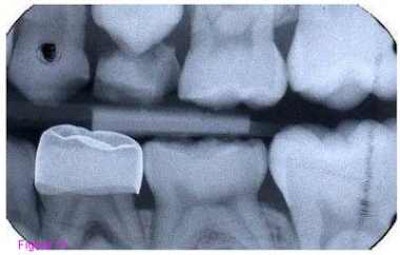

The study examined the Hall technique, in which dentists do not prepare the surface of the tooth they are treating or use anesthesia. Instead, they simply cement a preformed metal crown over the surface, sealing the cavity underneath.

The crown arrests the damage to the tooth, the researchers argue, because a complete seal with glass ionomer cement deprives the bacteria in the cavity of nutrients.

Upon follow-up of at least two years, 2% of the Hall technique teeth had signs and symptoms of irreversible pulpal disease compared to 15% of the conventionally treated teeth. Five percent of the Hall technique teeth failed because of caries progression or loss of the restoration, compared to 46% of the conventional restorations.

Though the crowns increased the heights of the treated teeth by about 2.5 mm, all the patients maintained full occlusal contact after treatment.